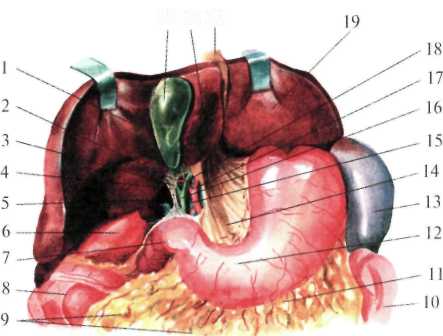

Брюшная часть пищевода, pars abdominalis oesophagei

Органы верхнего этажа брюшной полости

Брюшная часть пищевода от пищеводного отверстия диафрагмы (уровень X грудного позвонка) до перехода в желудок имеет длину 1—3 см. Адвентиция пищевода связана с медиальными ножками мышечного слоя диафрагмы. В результате сокращения ножек диафрагмы во время вдоха внутридиафрагмальный отдел пищевода закрывается, что препятствует регургитации (обратному забрасыванию) желудочного содержимого в пищевод. Ниже диафрагмы пищевод находится позади левой доли печени и тесно с ней соприкасается. На печени в этом месте имеется impressio oe-sophageale.

Здесь возможно внедрение проглоченных инородных тел через стенку пищевода в печень. Вместе с тем опухоль, развивающаяся в левой доле печени, может сдавливать пищевод.

Правый край пищевода плавно переходит в малую кривизну желудка, а левый край образует с дном желудка углубление, кардиальную вырезку, incisure cardialis, или угол Гиса [His] (рис.1.22).

Передняя поверхность брюшного отдела пищевода прикрыта листком брюшины, переходящим на него с диафрагмы. Под листком брюшины на передней поверхности брюшной части пищевода располагается передний блуждающий ствол, truncus vagalis anterior, а на задней — задний блуждающий ствол, truncus vagalis posterior. Задняя стенка пищевода, примыкающая к диафрагме, часто лишена брюшинного покрова.